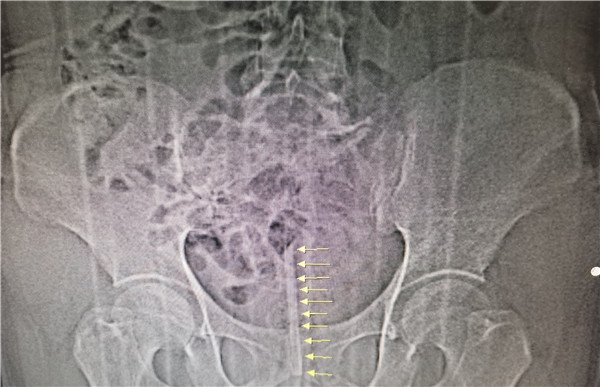

患者为一48岁男子,自诉因排尿不畅拟自行疏通,将一温度计塞入尿道,结果在“疏通”过程中温度计不慎折断,其中一截卡在尿道里面。经2天喝水排尿冲洗,无法自行排出,并渐出现血尿、尿*禁失**等症状。男子遂就诊于西安交大二附院泌尿外科门诊,付德来副主任医师了解情况后,考虑膀胱尿道异物,需紧急处理。付医生通过急诊通道为患者完善术前相关检查,同时联系病房,准备急诊手术。经CT检查显示膀胱残留温度计断端位于膀胱内。

手术在膀胱镜下实施,由付德来副主任医师、唐骁爽主治医师操作,王莉主管护师、姚媚媚护师、王清园护师的密切配合。术中看见温度计断端锐利,尿道局部粘膜已划伤出血。经过反复尝试并随机应变不断调整手术思路和策略,医生顺利将体温计断端导入膀胱镜鞘,并随膀胱镜鞘完整取出,手术历时30分钟。经测量残留温度计长约9cm,比对后确认温度计两断端对位良好,无碎块残留。

据了解,患者所用温度计为红水玻璃棒温度计,全长约30cm,直径约6.2mm,明显区别于常规的体温计。经查阅资料,红水玻璃棒温度计以煤油为工作介质,无重金属危害,这对患者来说也算是不幸中的万幸。